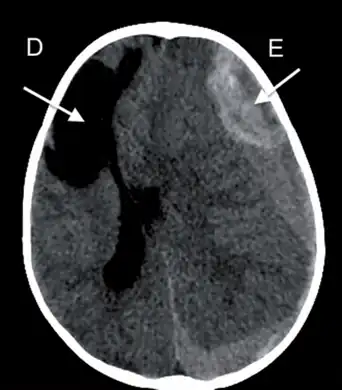

Subdural hemorrhage

Subdural hemorrhage (SDH) results from tearing of the bridging veins in the subdural space between the dura and arachnoid mater. It can cross the suture lines, but not across dural reflections such as falx cerebri or tentorium cerebelli.[4] Therefore, subdural hematoma always limited to one side of the brain.[3] Density of SDH reduces as it progresses from acute to chronic forms. However, areas with low density may not represent chronic SDH entirely as unclotted blood products that are due to active bleed can also give low density appearance on CT scans especially those with coagulopathy. Those with SDH that have same density with brain parenchyma may represent acute bleed such as those with anemia, arachnoid tear, and the mixing of hemorrhage and CSF. SDH usually have high or mixed densities during first two days of trauma, followed by isodensity at 11 days after trauma, and hypodensity after 14 days of trauma. Membranes with granulation tissue can rupture within SDH, and give high density appearance on CT scan. Over a prolonged period of time, calcifications can form. SDH can be treated with burr hole drainage, craniotomy or port system placement for blood clot evacuation, or middle meningeal artery embolisation.[4]

Subdural hematoma maybe less acute than epidural hematoma due to slower blood accumulation, but it still has the potential to cause brain herniation that may require surgical evacuation.[3] Clinical features depend on the site of injury and severity of injury. Patients may have a history of loss of consciousness but they recover and do not relapse. Clinical onset occurs over hours. Complications include focal neurologic deficits depending on the site of hematoma and brain injury, increased intracranial pressure leading to herniation of brain and ischemia due to reduced blood supply and seizures.